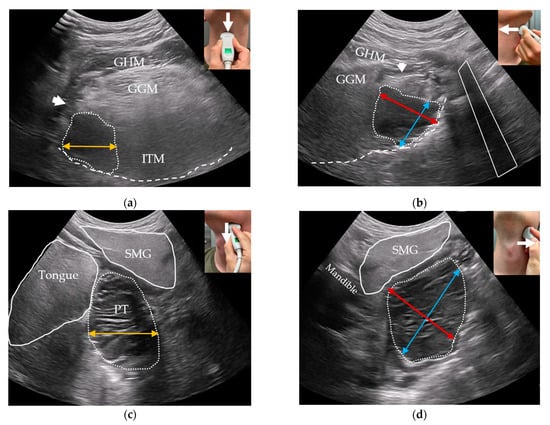

Following clinical examination, included patients will be offered combined transoral and transcervical US of the oropharynx during the initial work-up as an extension of the clinical work-up. This will be performed prior to any available T-site histopathology results. US will be performed blinded to any cross-sectional imaging. To perform the transoral US, a patient seated upright in an examination chair will receive topical anesthetic spray applied to both palatine tonsils and the posterior portion of the tongue using xylocaine (10 mg/dose). Patients are informed that eating or drinking following local anesthesia should be postponed for up to one hour due to the risk of aspiration. Patients are instructed to swallow the anesthesia. A sheathed or disinfected “hockey-stick” or small-footprint US transducer is advanced into the patient’s mouth and placed on top of the suspected palatine tonsil in the transverse plane (Figure 1a,c) with a gentle swiping motion from the cranial to caudal pole. The transducer is rotated to the sagittal plane by positioning the tip of the transducer caudally (Figure 1b,d) and a swipe is performed from the lateral to the medial edge. The procedure is repeated contralaterally. Power Doppler is performed on both palatine tonsils. If a lingual tonsil tumor is suspected, a transoral US is attempted (Figure 2).

Figure 1. Transoral US of the palatine tonsils: (a) a sheathed US transducer placed on the right palatine tonsil (arrow: swipe direction cranial-to-caudal) in the transverse plane; (b) sagittal plane (arrow: swipe direction lateral-to-medial); (c) transverse US image with Power Doppler of a right palatine tonsil tumor (dotted outline) with underlying constrictor muscle (dashed line), internal carotid artery (ICA), stylopharyngeus muscle (SPM), styloglossus muscle (SGM), and medial pterygoid muscle (MPM). The anteroposterior (red bi-directional arrow) and mediolateral (orange bi-directional arrow) tumor diameters are shown; (d) sagittal US image of the same tumor (dotted outline) with the underlying constrictor (dashed line), ICA, and MPM. In sagittal view, the MPM can be used as a craniolateral landmark. The craniocaudal diameter of the tonsil is shown using a blue bi-directional arrow.

All US tumor measurements will be registered blinded to MRI and PET/CT. Small tumors will be measured transorally if they fit within the field-of-view of the transoral US transducers. In transverse transoral US of the palatine tonsils, the medial pterygoid muscle will serve as a lateral landmark (Figure 1c): the mediolateral diameter will be measured from the medial pterygoid muscle towards the tonsil’s medial surface. A perpendicular measurement will be performed for the anteroposterior diameter (Figure 1c). In sagittal view, the length of the tonsil tumor from the upper to lower pole will be measured as the craniocaudal diameter (Figure 1d). For the lingual tonsil, the hyoid bone will serve as a caudal landmark for the craniocaudal tumor diameter (Figure 2b). A perpendicular anteroposterior diameter will be measured through the tumor from the posterior surface of the lingual tonsil in the direction of the tongue apex. The mediolateral diameter is more difficult to measure transorally due to technical limitations of the US transducers. Instead, this diameter will be measured transcervically if the tumor can be visualized.